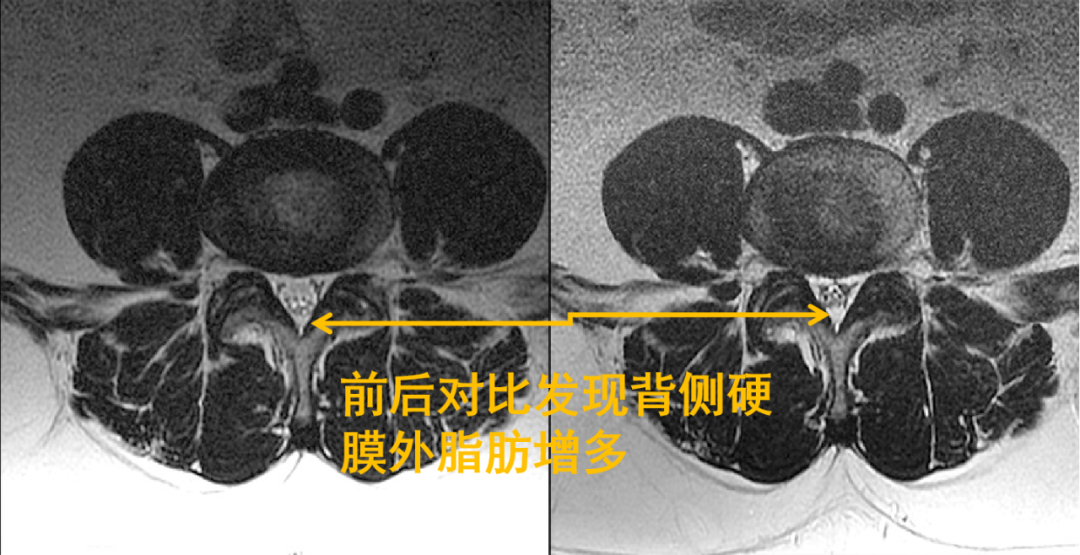

回过头再看第二个病例,发现椎管内背侧硬膜外脂肪增多,超过椎板前缘,向前推挤马尾神经,使其明显聚拢

轴面上 T2WI 收到硬膜外脂肪的推挤,硬膜囊可以发生变形(正常为椭圆形)通常为多边形(A)、星状(B)或 Y 形或 V 形(C-D)

同样的,回头看第一个病例也会发现硬脊膜椎韧带,是由于硬膜外脂肪增多而把他显示出来